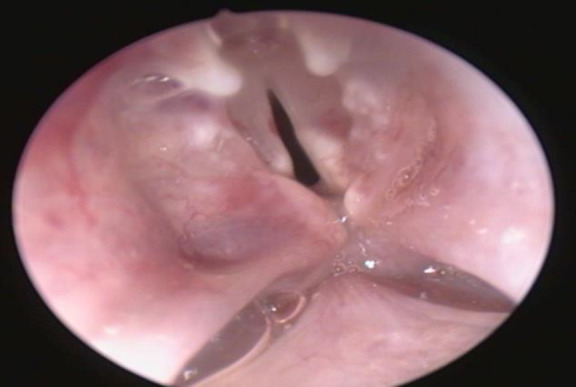

Materials and methods: Ten rabbits were included in this experimental study. A thermal injury was created at the posterior commissure using a conchal probe. Following the injury, one group was treated with mitomycin-C, while the other received epirubicin. After a six-week post-treatment period, the rabbits were euthanized, and both macroscopic and microscopic evaluations were performed to assess stenosis, scarring, granulation tissue, necrosis, and ulceration. Two pathologists, blinded to the treatment groups, independently examined the histological samples.

Results: Macroscopically, no significant differences were observed between the two groups in terms of scarring, synechiae, or granulation tissue formation at the posterior commissure. However, the mitomycin-C group demonstrated a relatively milder tissue response. Microscopic analysis revealed grade 3 collagen deposition in one rabbit and grade 1 in two rabbits from the epirubicin group. In comparison, the mitomycin-C group showed grade 1 deposition in two rabbits and grade 2 in another two. The average fibroblast count was 83.3 in the epirubicin group versus 59 in the mitomycin-C group.